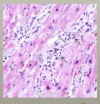

The provided image shows what histology?

normal myocardium